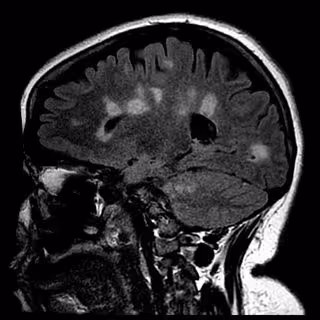

Identifican una molécula que podría ser responsable de las recaídas de la esclerosis múltiple

Cicatrización del cerebro en la esclerosis múltiple

UNIVERSITY OF BRITISH COLUMBIA - Archivo